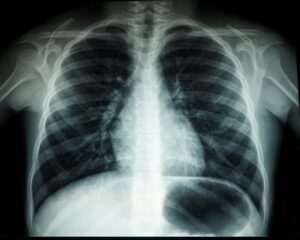

L’imagerie médicale au beau fixe

Première bonne nouvelle, en 2016, le marché français de l’imagerie médicale a progressé de 5%. Comme une bonne nouvelle vient rarement seule, Xerfi annonce également dans la foulée que ce même marché évoluera à la hausse et dans les mêmes proportions en 2017, mais aussi en 2018, 2019 et 2020.